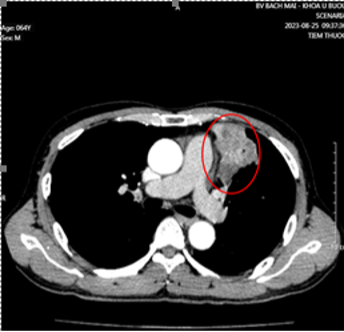

Msct toàn thân có tiêm thuốc cản quang

Dầy thành thực quản 15mm kéo dài 1/3 cuối thực quản, bắt thuốc cản quang mạnh, chùm hạch lớn vùng đầu tụy 5cm

Hạch 14mm vùng thượng đòn trái